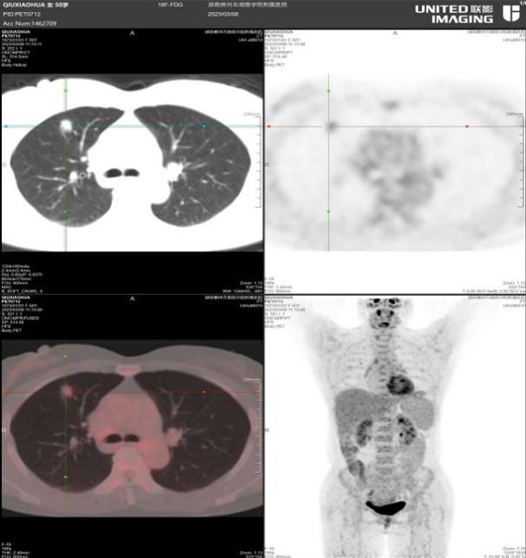

PET-CT是目前最先进的核医学分子设备,与传统影像学相比,其具有灵敏度高、分辨率好、图像清晰、性能稳定、辐射量小等特点,可以根据实性肺结节代谢情况,区分良恶性,一次性完成肺部病灶排查,更灵敏、更准确、更早期地发现病灶,此外还可筛查肿瘤是否存在转移,为患者提供更精准的治疗。

PET-CT检查结果出来后,提示右肺癌可能性大,王女士转入湘南学院附属医院肿瘤科进行系统治疗,随后通过术后病理检查确诊为右肺腺癌。正因为经过早期的精准筛查和诊治,王女士术后恢复顺利,现已康复出院。